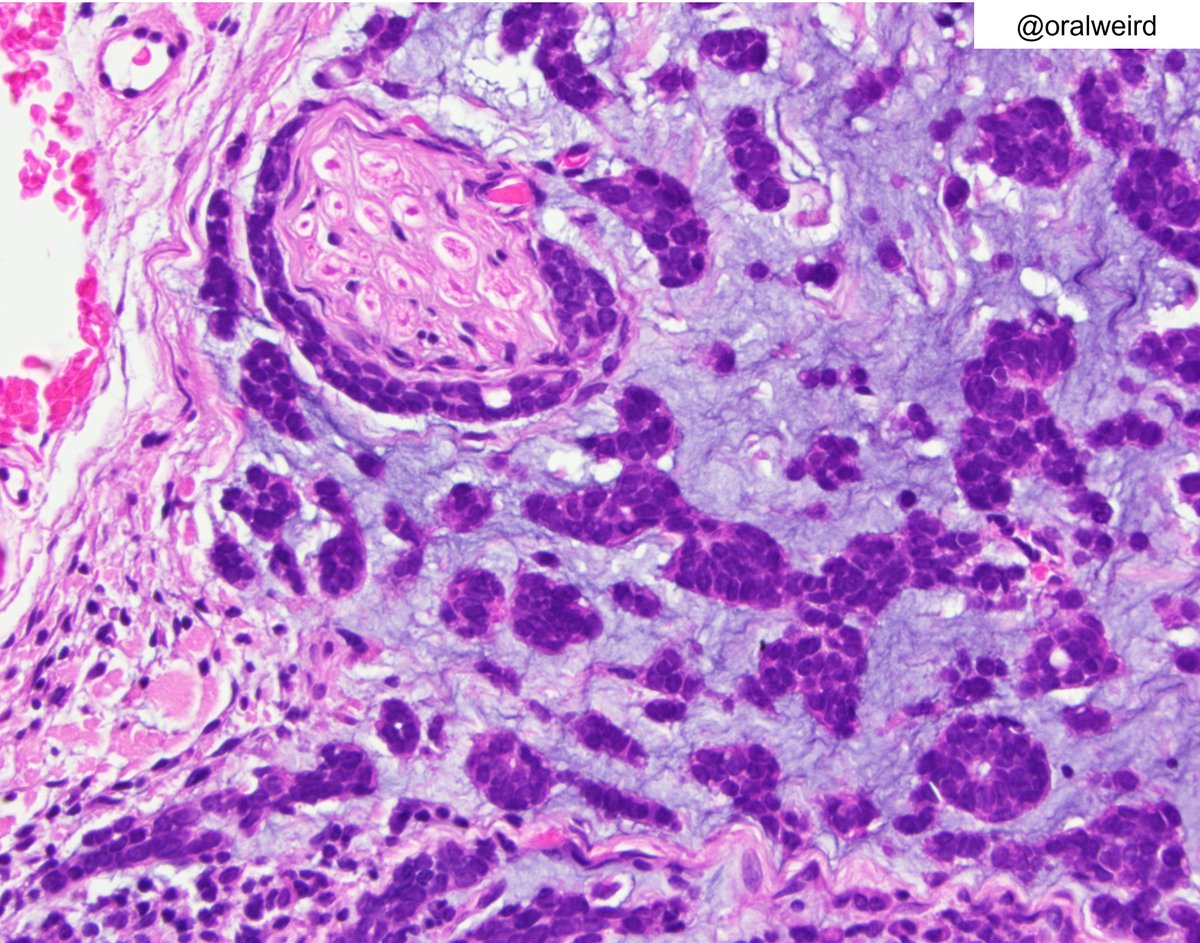

Basaloid squamous cell carcinoma of the oral cavity showing comedonecrosis. The differential diagnosis includes solid variant of adenoid cystic carcinoma and neuroendocrine carcinoma #oralpath #entpath #pathology